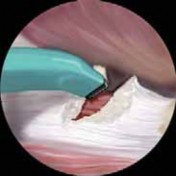

B C TECH FIG 4•

Endoscopic method of iliotibial band tendoplasty, shown in the right hip.

A.

After creating the longitudinal incision, the anterior limb is created by a perpendicular incision.

B.

Resecting the edges creates a triangle that aids in visualization of the underlying structures.

C.

The posterior limb is then created, and resection completes the diamond pattern of the tendoplasty. (Adapted from Ilizaliturri VM Jr, Martinez-Escalante FA, Chaidez PA, et al. Endoscopic iliotibial band release for external snapping hip syndrome. Arthroscopy 2006;22:505–510.)